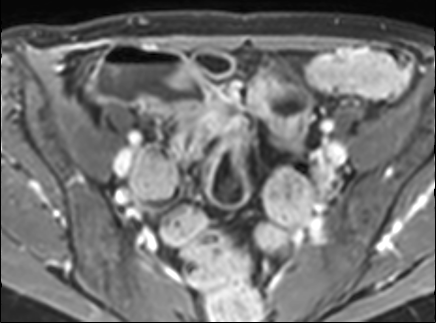

Hồi tràng cuối đang viêm cấp tính với dày thành nhiều và tín hiệu thành ruột vừa (phù nề thành ruột) trên hình ảnh T2 axial có fat-sat.

Tăng tín hiệu thành ruột trên hình ảnh T2W có fat-sat cho thấy sự hiện diện của phù nề thành ruột, gợi ý bệnh đang hoạt động.

Dày thành ruột kèm giảm tín hiệu T2W thành ruột gợi ý nhiều hơn đến bệnh xơ hóa.